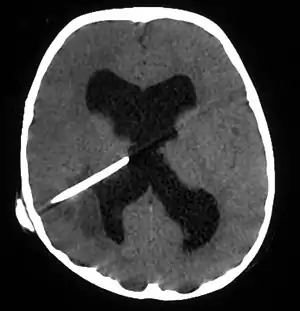

| Brain abscess in a person with a CSF shunt.[1] | |

The diagnosis is established by a computed tomography (CT) (with contrast) examination. At the initial phase of the inflammation (which is referred to as cerebritis), the immature lesion does not have a capsule and it may be difficult to distinguish it from other space-occupying lesions or infarcts of the brain. Within 4–5 days the inflammation and the concomitant dead brain tissue are surrounded with a capsule, which gives the lesion the famous ring-enhancing lesion appearance on CT examination with contrast (since intravenously applied contrast material can not pass through the capsule, it is collected around the lesion and looks as a ring surrounding the relatively dark lesion). Lumbar puncture procedure, which is performed in many infectious disorders of the central nervous system is contraindicated in this condition (as it is in all space-occupying lesions of the brain) because removing a certain portion of the cerebrospinal fluid may alter the concrete intracranial pressure balances and causes the brain tissue to move across structures within the skull (brain herniation).

Ring enhancement may also be observed in cerebral hemorrhages (bleeding) and some brain tumors. However, in the presence of the rapidly progressive course with fever, focal neurologic findings (hemiparesis, aphasia etc.) and signs of increased intracranial pressure, the most likely diagnosis should be the brain abscess.